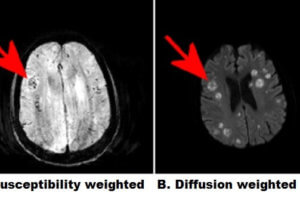

Septic Emboli

There is an extensive differential for multifocal T2/FlAIR hyperintense lesions in the brain parenchyma including neoplasm (metastasis, lymphoma), infection (abscess, septic emboli), infarct (vasculitis), trauma (diffuse axonal injury) and demyelinating disease (multiple... Read more »